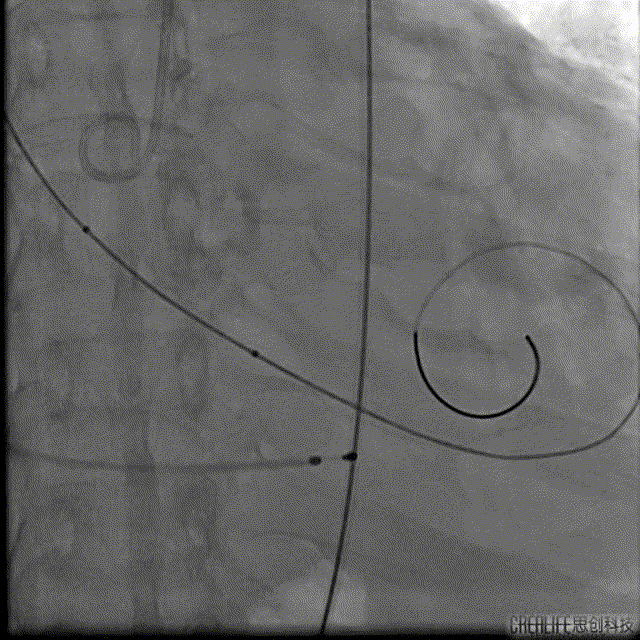

Numed25预扩

Venus32上跳